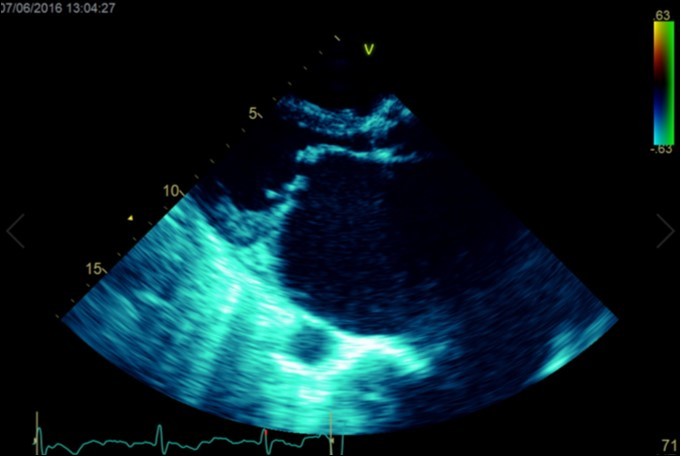

Figure 2a.Transthoracic echocardiogram Apical 4C view. Findings include severely enlarged left atrium, severe mitral stenosis with associated regurgitation, a mean gradient across the valve of 11mmHg with a hyperdynamic left ventricle

Transthoracic echocardiogram Apical 4C view. Findings      include severely enlarged left atrium, severe mitral stenosis with                  associated regurgitation, a mean gradient across the valve of 11mmHg with a hyperdynamic left ventricle

A dramatically dilated left atrium was seen on a TTE (see Figure 2a, Figure 2b, Figure 2c, and Figure 2d). Severe mitral stenosis with associated regurgitation was evident, with a mean gradient across the valve of 11mmHg and a hyperdynamic left ventricle. The left atrial volume measured by Simpson’s biplane method (see Figure 2c) was 2108mL, or 1548.5 ml/m2, based on height 1.55 metres and weight 44 Kg. Normal left atrial volume in a woman is 16 - 34 ml/m21. The computed tomography scan (CT) chest AP view (see Figure 3) is also shown.